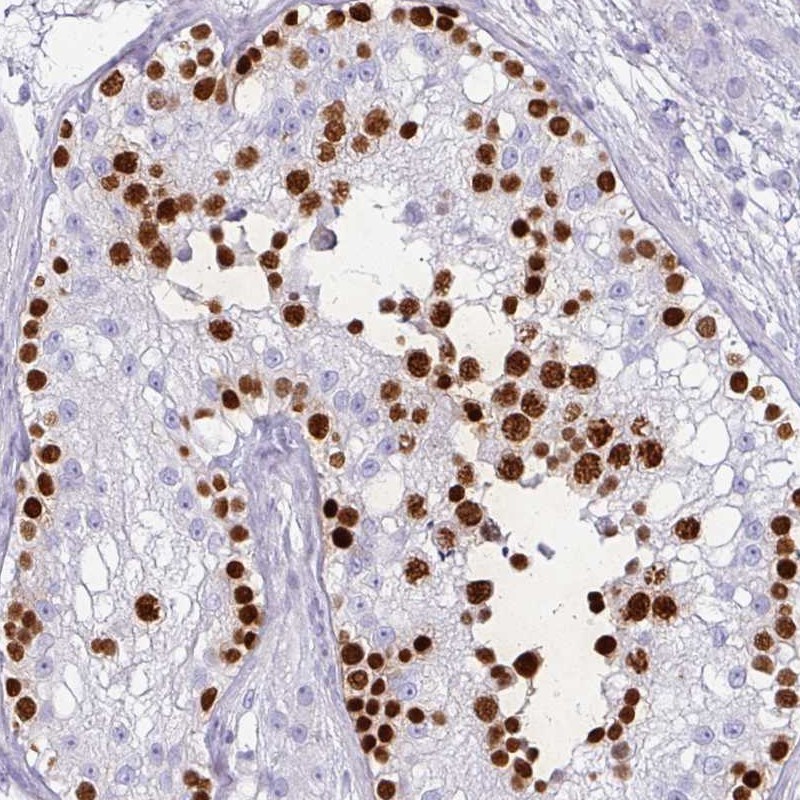

Immunohistochemical staining of human testis shows strong nuclear positivity in cells in seminiferus ducts.